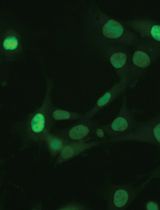

TRIPLE (Insulin, Glucagon and EGFP) Immunofluorescence Staining Protocol in Pancreas

胰腺的三重(胰岛素、胰高血糖素和增强型绿色荧光蛋白(EGFP))免疫荧光染色法

Cover of Nature Cell Biology, featuring study using the protocol.

May 2013